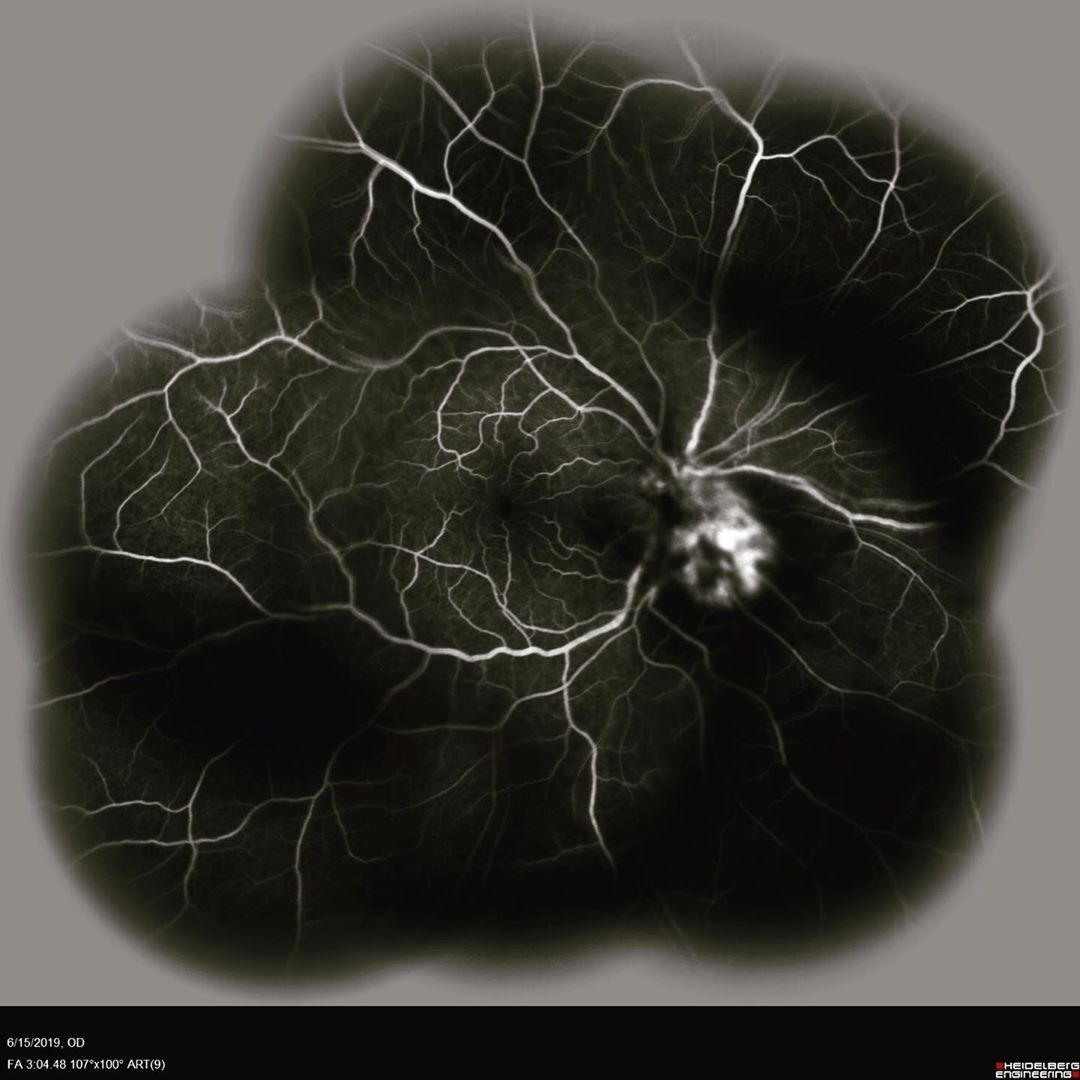

.@icare_usa released two new, next-generation imaging and tonometry devices: CenterVue DRSplus confocal fundus imaging system and

Icare ic200 handheld tonometer for portable measurement of IOP. buff.ly/2WwYbOi #optometry